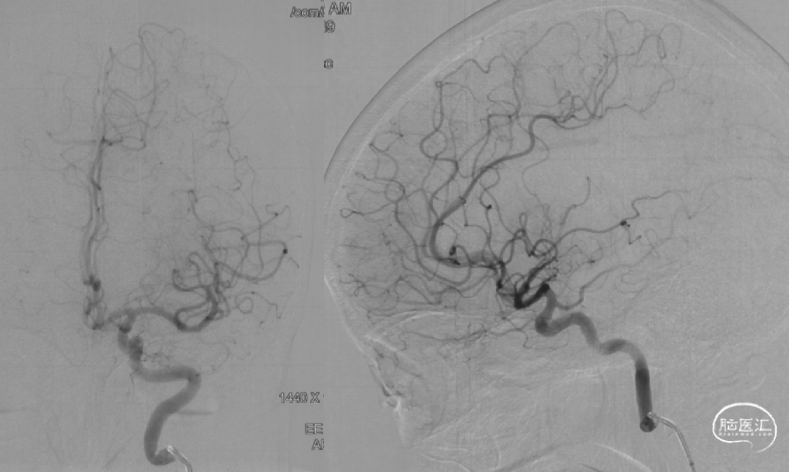

CTA提示右侧大脑中动脉M2远端闭塞,近端血管迂曲。

颈内动脉造影提示颈内动脉颈段迂曲,大脑中动脉下干M2远端闭塞,颞顶部可见乏血管区。